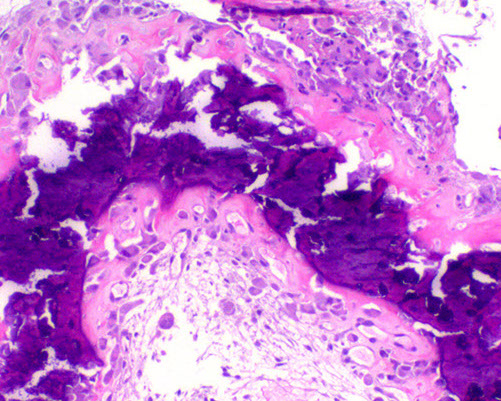

Micro: malignant bone stroma with lacy-patterned matrix that at least focally produces osteoid surrounding neoplastic mesenchymal cells and is infiltrating the marrow spaces bwt mature trabeculae

- can see atypical mits (atypical mits NEVER in b9 conditions [?])

- normalization: atpia is less in oseoid islands than in surrounding malignant stroma

Any amount of neoplastic matrix automatically upgrades a lesion to osteosarcoma

MC subtype is conventional high-grade type (made mostly of osteoblastoma; 75-85%); then high-grade secondary osteosarcoma (10%) and surface osteosarcoma (5-10%) - [chondroblastic {makes cartilage}, fibroblastic {no matrix production}, small-call or giant-cell rich]

Osteosarcoma